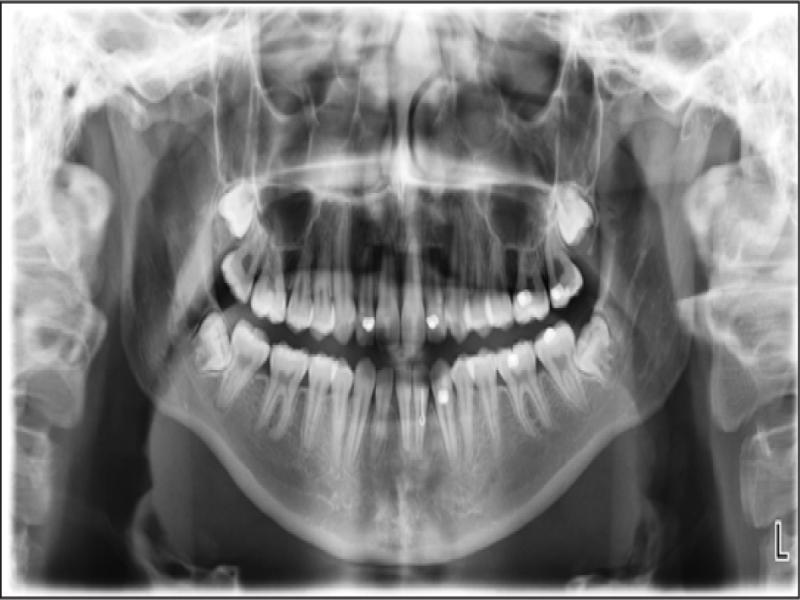

A radiographic examination was unremarkable on the OPG (Figure 2). Cephalometrically (Figure 3, Table I) a Class III skeletal relationship was evident, with a Wits discrepancy of -2.1 mm (due primarily to maxillary retrusion – SNA 72.6°). However, the Class III was camouflaged by the significant vertical disproportion, highlighted by an increased mandibular plane angle (28.6°), reduced facial axis angle (83.2°), reduced Jarabak’s ratio (56.5%), and increased lower anterior facial height (53.4%), all of which indicated a dolichofacial pattern. The maxillary retrusion, combined with a mandibular downward and backward rotation, resulted in a bimaxillary retrusive skeletal relationship (SNB 72.6°). The upper incisors were at an acceptable angulation relative to the palatal plane (112°) and the anteroposterior position relative to Na-Vert. The lower incisors were at an acceptable position relative to APo but were retroclined relative to the mandibular plane (80.7°) according to mesofacial norms.

Pretreatment OPG.